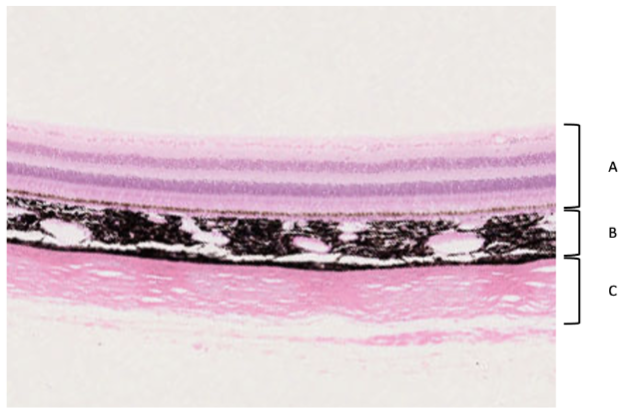

Ögat indelas i tre lager, och bilden visar dessa lager i den bakre delen av ögat (A-C).

Om man följer respektive lager mot den anteriora (främre) delen av ögat övergår dessa i olika strukturer. Vilka? Svara på frågorna genom att välja det rätta/bästa alternativet för varje lager: a) Lager A kommer att övergå i (epitel, hornhinna, ciliarkropp, iris) b) Lager B kommer att övergå i (iris, conjunctiva, hornhinna, iris, epitel) c) Lager C kommer att övergå i Hornhinna (epitel, iris, Hornhinna, ciliarkropp) d) I vilket lager finns muskulatur? (A, B, C) (0,25p per rätt svar, totalt 1 p)